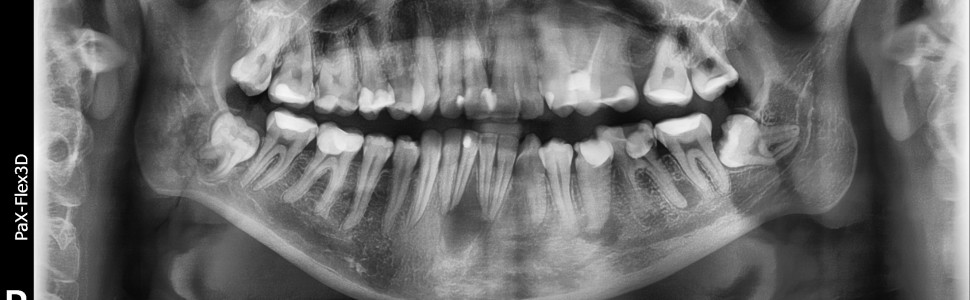

Zachowawcze leczenie rozległej torbieli korzeniowej zębów siecznych w żuchwie z użyciem lasera diodowego o długości fali 940 nm

Zmiany osteolityczne o charakterze torbieli korzeniowych są spowodowane zakażeniem pochodzenia bakteryjnego. Głównymi patogenami wywołującymi torbiele są bakterie kompleksu czerwonego oraz zielonego o dużym potencjale osteolitycznym. Zmiany okołowierzchołkowe mają szanse na wygojenie podczas zastosowania antyseptycznego protokołu endodontycznego skierowanego na konkretne patogeny. Znajomość patomechnizmu działania osteolitycznego bakterii beztlenowych oraz endotoksyn bakteryjnych pozwala na wykorzystanie skutecznych metod zachowawczych w celu wyleczenia procesu zapalnego. Poza koniecznym antyseptycznym leczeniem endodontycznym ogromne znacznie ma terapia wspomagająca. Torbiele korzeniowe mogą ulec regresji poprzez mechanizm apoptozy w sposób podobny do ustępowania pozostałych zmian okołowierzchołkowych bez konieczności wdrażania inwazyjnego leczenia chirurgicznego.

Osteolytic lesions of the nature of root cysts are caused by infection of bacterial origin. The main pathogens causing cysts are red and green complex bacteria with high osteolytic potential. Periapidermal lesions have a chance of healing when using an antiseptic endodontic protocol directed at specific pathogens. Knowledge of pathomechnism of osteolytic action of anaerobic bacteria and bacterial endotoxins allows the use of effective conservative methods to cure the infl ammatory process. In addition to the necessary antiseptic endodontic treatment, supportive therapy is extremely important. Root cysts may regress by apoptosis in a manner similar to the resolution of other peri-apex lesions without the need for invasive surgical treatment.